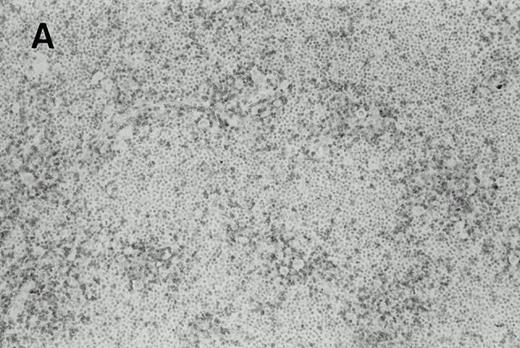

In case 1, the cervical lymph nodes showed a proliferation of small lymphocytes with round nuclei, consistent with CLL. In addition, large highly pleomorphic cells resembling H-RS cells were present in small clusters among small lymphocytes (Fig 1A).In case 2, the lymph nodes showed subtotal obliteration of the architecture by a polymorphic infiltrate of small lymphocytes and histiocytes, with scattered H-RS cells admixed. In case 3, an axillary lymph node exhibited nodules of HD, with H-RS cells present in a typical polymorphous inflammatory background (Fig 1B), which was sharply delineated from areas with CLL.

H-RS cells in case 1 (A) and case 3 (B), (hematoxylin and eosin, original magnification × 400). H-RS cells were present among small lymphocytes in case 1, whereas they were present in a polymorphous inflammatory background in case 3.